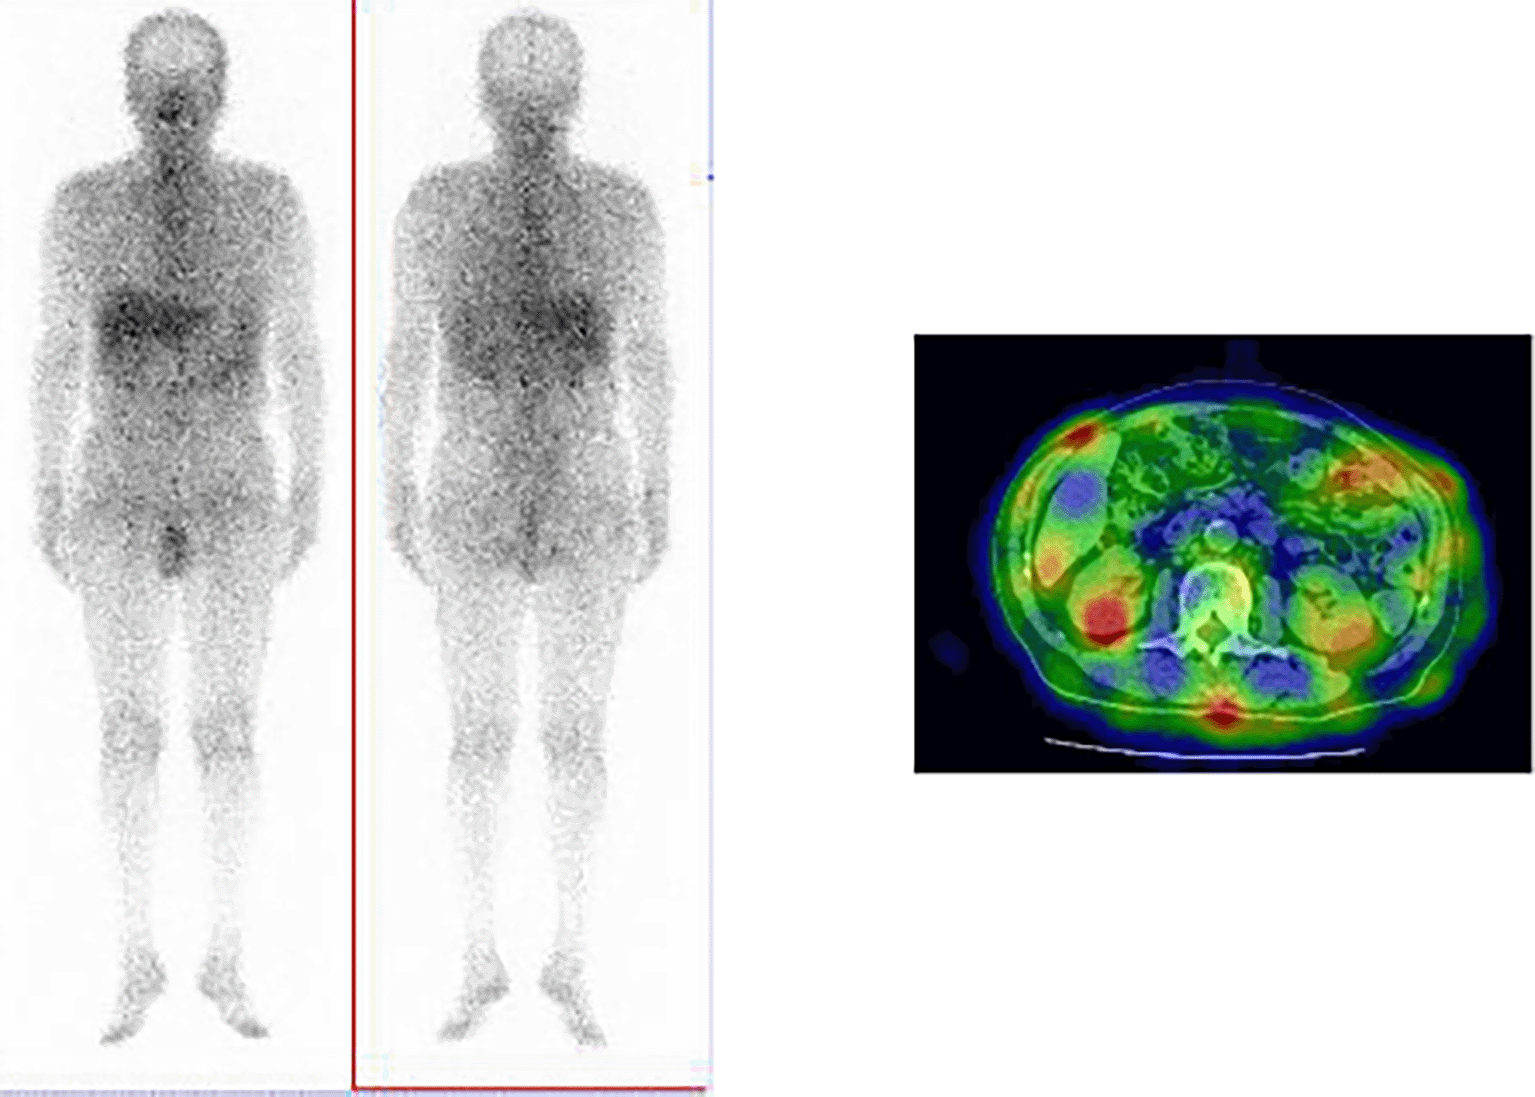

An 84-year-old unemployed Japanese man presenting with dyspnea on exertion and cough was referred to our hospital. The patient had a history of hypertension and hypothyroidism, but an unremarkable family history of any related pathology. Examination results of the patient were found to be negative for arthralgia, skin rash, macrohematuria, and hemoptysis. Upon admission, body temperature was recorded to be 36.5 °C; blood pressure, 128/72 mmHg; heart rate, 72 bpm; oxygen saturation, 98%; weight, 60.5 kg; height, 164.9 cm; and BMI, 21.1 kg/m2. Initial laboratory and diagnostic workup revealed blood urea nitrogen 18 mg/dL (normal range: 8-20 mg/dL), creatinine 0.98 mg/dL (normal range: 0.65-1.07 mg/dL), estimated glomerular filtration rate 56 mL/min/1.73 m2 (normal range: ≥ 60 mL/min/1.73 m2), calcium 9.4 mg/dL (normal range: 8.8-10.4 mg/dL), total protein 9.1 g/dL (normal range: 6.5-8.0 g/dL), albumin 3.6 g/dL (normal range: 3.9-4.9 g/dL), alkaline phosphatase 60 IU/L (normal range: 50-350 IU/L), aspartate transaminase 27 IU/L (normal range: 7-38 IU/L), alanine transaminase 11 IU/L (normal range: 4-44 IU/L), total cholesterol 182 mg/dL (normal range: 120-220 mg/dL), triglyceride 175 mg/dL (normal range: 50-149 mg/dL), WBC 11.5×103/μL (normal range: 3.1-8.4×103/μL), RBC 3.97×106/μL (normal range: 4.2-5.7×106/μL), hemoglobin 12.5 g/dL (normal range: 14-18 g/dL), platelets 200×103/μL (normal range: 150-330×103/μL), eosinophils 3% (normal range: 0-5%), and urinalysis negative for protein, RBC, and cell casts. Urinary N-acetyl-beta-D-glucosaminidase (NAG)/creatinine 17.1 IU/gCr (normal range: 1.6-5.8 IU/gCr) and urinary β2 microglobulin 371 mg/L (normal range: ≤289 mg/L). Antineutrophil cytoplasmic antibodies screening was found to be negative, with low C3=68 mg/dL, low C4=7.4 mg/dL, and negative for anti-SSA, anti-SSB, anti-RNP, Scl-70, anti-Sm, and ds-DNA antibodies. Antinuclear antibodies (ANA) antibodies were found to be ×1280. Hyperglobulinemia was determined with an IgG level of 3719 mg/dL (normal range: 870-1700 mg/dL) and an IgG4 level of 1290 mg/dL (normal range: 4-108 mg/dL). Rheumatoid factor (≤15 IU/mL) was elevated at 24 IU/mL, and KL-6 (<500 IU/mL) was significantly increased at 623 IU/mL. Computerized tomography (CT) revealed bilateral ground-glass and reticular opacities predominantly in the lower and peripheral portions of the lungs (Figure 1a). Furthermore, bronchial wall thickening, and enlarged cervical, mediastinal, and axillary lymph nodes were identified. However, renal, pancreatic, or salivary gland inflammation was not observed. Ga-67 scintigraphy revealed accumulation in the kidneys (Figure 2). Consequently, the patient was diagnosed with IgG4-related kidney disease based on the renal pathology with massive tubulointerstitial nephritis, characteristic fibrosis (bird’s eye pattern) (Figure 3a and b), and IgG4-positive cell infiltration, wherein the number of IgG4 positive plasma cells was >10/hpf, and IgG4/IgG ratio was 61.9% (Figure 3c). Deposition of globulin or complement, and evidence of glomerular sclerosis were not observed in the glomeruli. Treatment was initiated by administering oral prednisolone at 30 mg/day for one month, followed by prompt alleviation of cough and dyspnea on exertion. With a subsequent decrease (after one month prednisolone treatment) in urinary NAG and β2 microglobulin and IgG4 levels, prednisolone was decreased from 2.5 to 5 mg every 2 to 4 weeks for 4 weeks. One year after the initiation of treatment, the patient achieved normalization of serum IgG4 levels, and chest CT revealed the interstitial pattern was found to have nearly disappeared (Figure 1b). Figure 4 shows the clinical course of this patient.

Similar to the present case, approximately 30% of the patients diagnosed with IgG4-related kidney disease do not show any abnormality on a CT scan. In contrast, previous reports indicated that approximately 70% of patients with IgG4-related kidney disease show some kind of abnormality.9,12 The discrepancy between these findings can be owing to the presence or absence of contrast-enhanced CT, which is necessary within renal function tolerance. Ga-67 scintigraphy and FDG-PET have been reported to be useful for its diagnosis. However, contradictory to the present case, positive accumulation in the kidney during Ga-67 scintigraphy has been reported to be only 11%.9 Another useful method of analysis for IgG4-related kidney disease is T2-weighted and diffusion-weighted MR imaging.13